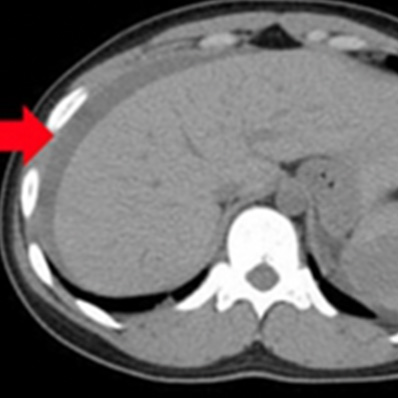

急性大動脈解離

(StanfordA型)